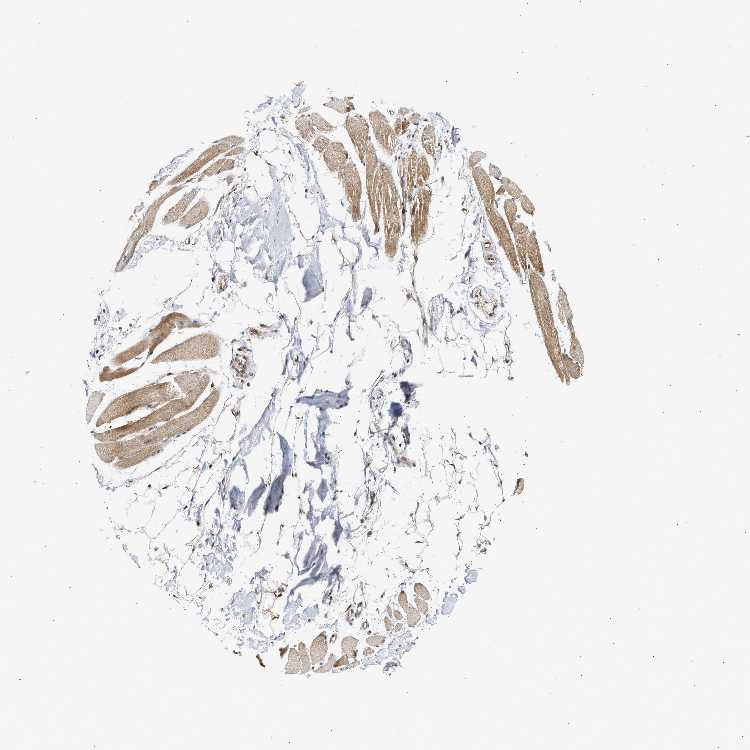

SKELETAL MUSCLE - Antibody stainingi

Antibody staining in the annotated cell types in the current human tissue is reported as not detected, low, medium, or high, based on conventional immunohistochemistry profiling in selected tissues. This score is based on the combination of the staining intensity and fraction of stained cells.

Each image is clickable and will lead to virtual microscopy that enables deeper exploration of all samples and also displays staining intensity scores, fraction scores and subcellular localization as well as patient and tissue information for each sample.

Antibody CAB020716

Myocytes Medium